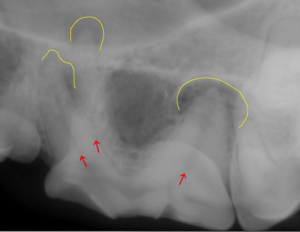

● 歯の破折 3 : 根先膿瘍の放置による目の下の開放創

根先膿瘍は放置することで目の下に穴が空くことがあります。

この3枚の写真に示されるように①は根先部に膿瘍が認められます。②は膿瘍部分に黄色く色づけをしてみました。③は逆サイドの正常な写真になります。![]()